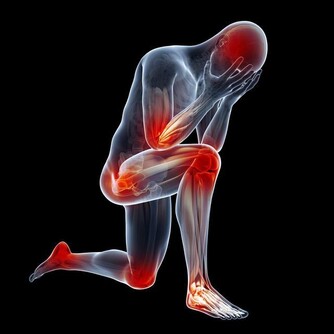

• 口腔潰瘍前後伴有脫髮,顏面部紫紅斑,關節疼痛等症狀時可能是紅斑狼瘡所致。